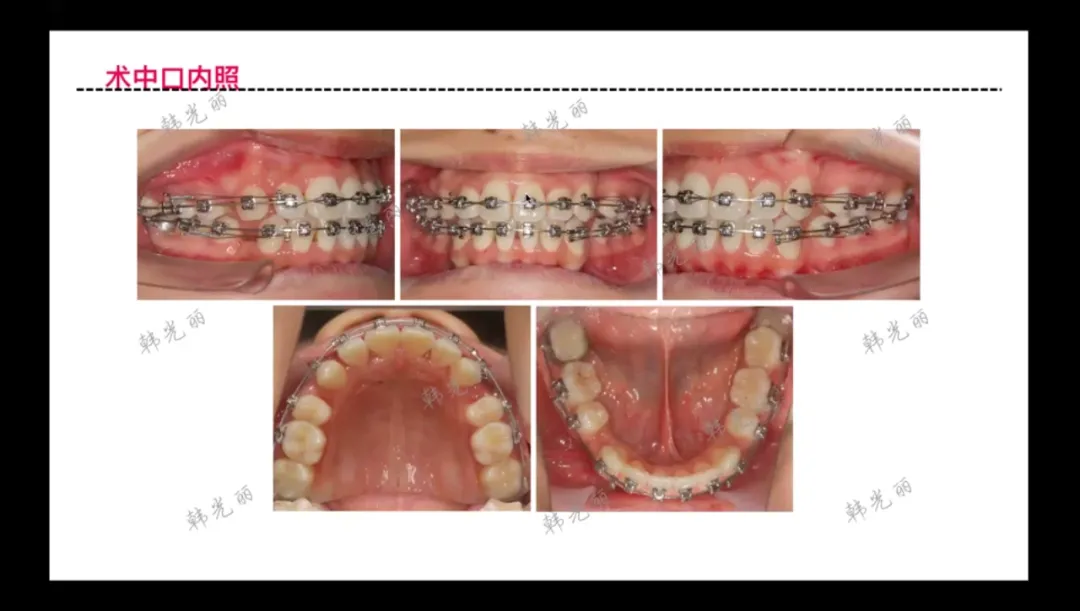

• 初始方法

:采用滑动法关闭间隙,使用中重度支抗进行控制

• 力学控制

:通过种植钉(粽子丁)实现控根和力学方向调整,重点控制上颌骨及牙根部